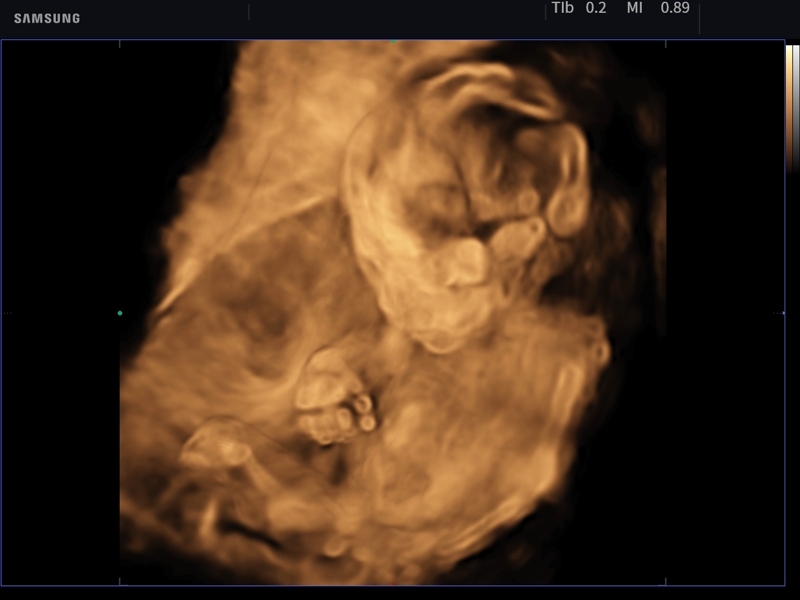

• Модуль Realistic Vue - программа реконструкции реалистичного 3D УЗИ, при котором на объемное изображение накладывается виртуальный источник освещения. Специальный процессинговый алгоритм воспроизводит трехмерную анатомию плода с исключительной детализацией.

• Модуль Crystal Vue - программа реконструкции прозрачного 3D УЗИ, которое получается при одновременном усилении внутренних и наружных структур. Применяется для визуальной оценки состояния плода и матки, помогает лучше идентифицировать мягкие ткани и кости.